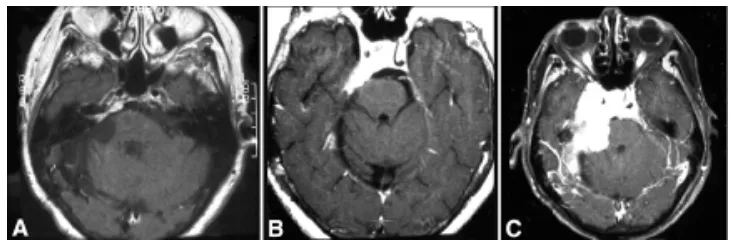

该56岁女性患者于1981年接受右侧蝶岩斜区脑膜瘤切除术。1991年(66岁时)随访MRI显示内听道内侧及上方出现小型肿瘤复发(图1A)。

图1.56岁女性患者,曾接受右侧蝶岩斜区脑膜瘤切除术,磁共振影像显示肿瘤进展。A:10年后随访影像显示内听道内侧及上方出现小型肿瘤复发,接受伽玛刀治疗。B:病灶稳定8年后,患者出现右侧面部感觉异常、面肌痉挛及进行性共济失调。C:2年后随访影像显示肿瘤进展。

患者接受伽玛刀治疗。影像学随访保持稳定直至1999年,出现右侧面部感觉异常、面肌痉挛及进行性共济失调(图1B)。2001年随访影像学检查显示脑膜瘤在过去两年显著进展(图1C)。肿瘤累及右侧岩斜缘,延伸至右侧海绵窦及视神经管,并填充蝶鞍,向左侧海绵窦延伸。临床再评估显示症状进展:右侧面肌无力加重,第Ⅲ、Ⅴ、Ⅵ对颅神经右侧不全麻痹,伴发声及轻度构音障碍。